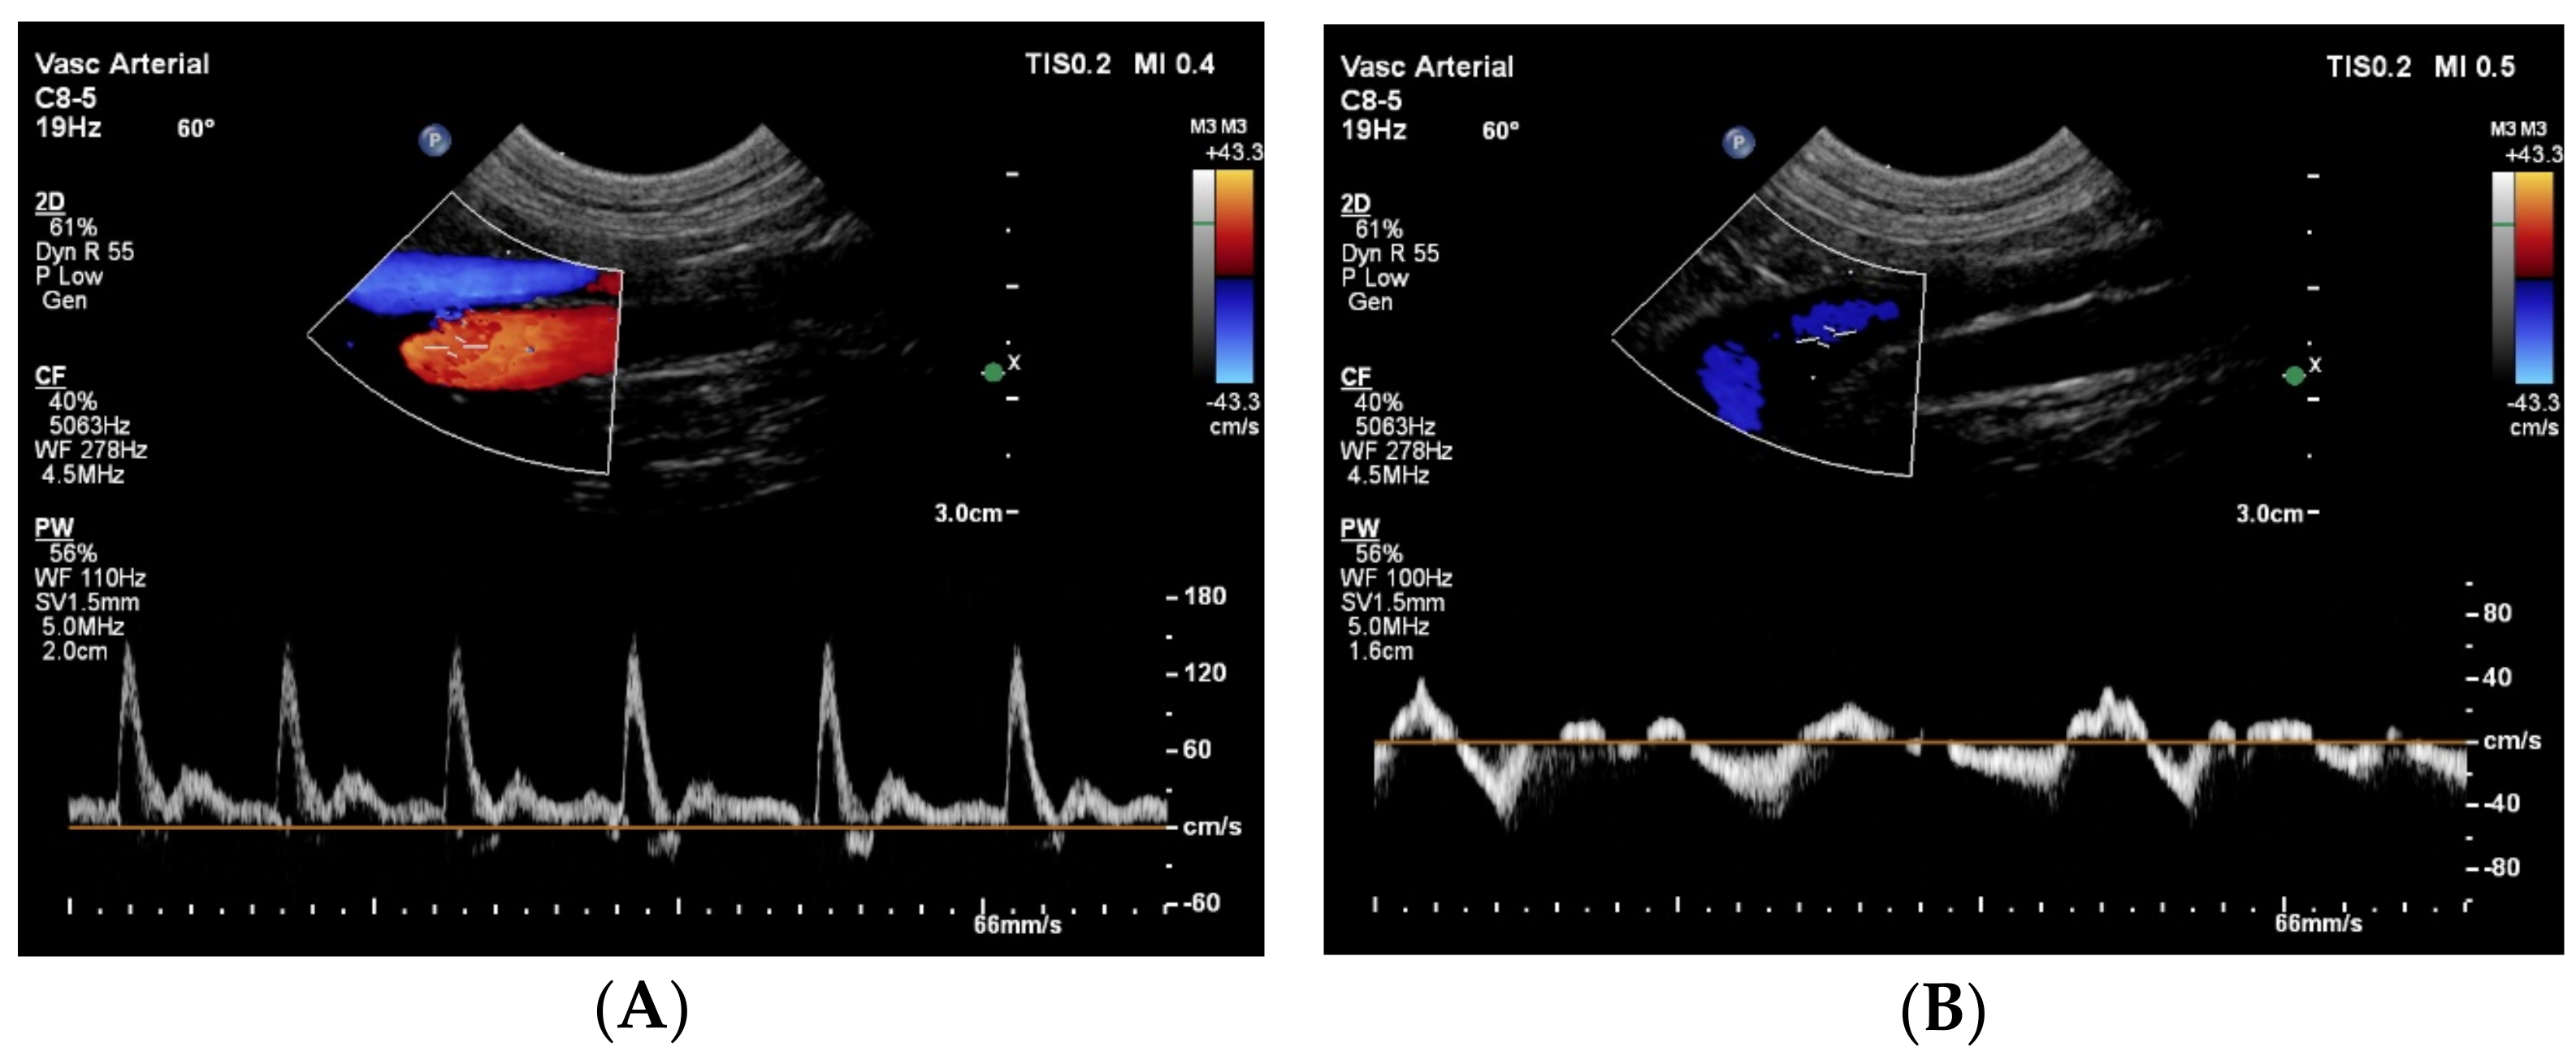

The CVC in the cranial abdomen showed an extreme aneurysm with a diameter up to 45 mm, with blood stasis to sluggish blood flow with spontaneous echo contrast in it (Figure 3). No thrombus was noted.

Figure 3. Two-dimensional grey-scale ultrasound images show an aneurysm of the azygos vein dorsal to the right kidney in longitudinal (A) and in cross section (B). In the vessel, spontaneous echo contrast is visible because of the blood stasis and sluggish flow. The images were obtained via the right lateral abdominal wall with the dog in left lateral recumbency. These findings suggest a severe venous obstruction downstream (i.e., cranial) to this location.